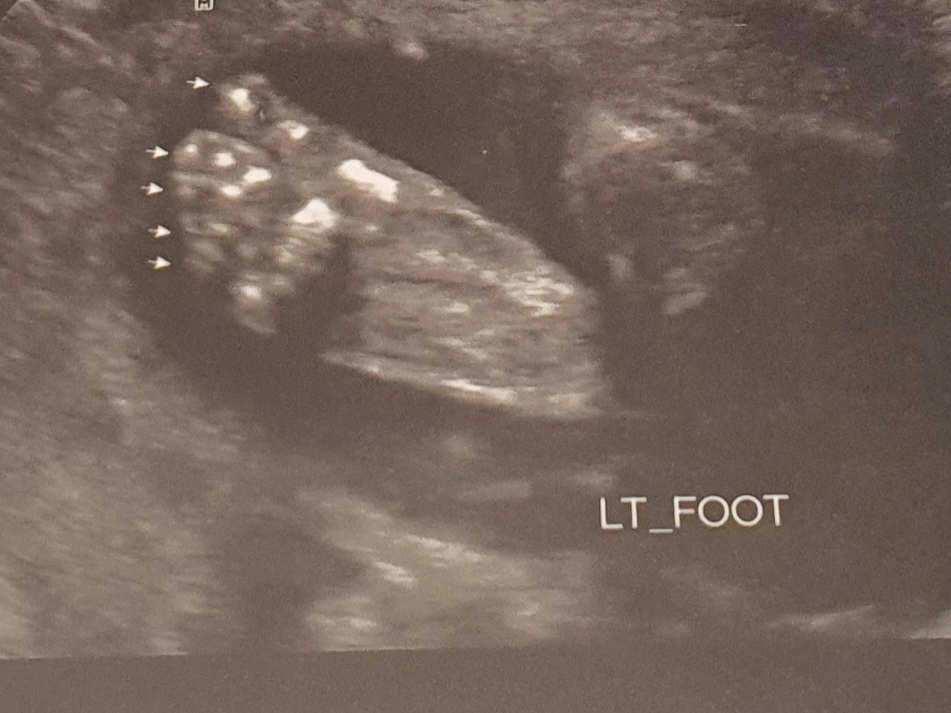

채혈이 끝나고 정밀초음파를 보러 갔다. 평소에 보는 초음파와는 다르게 시간이 좀 걸렸다. 20~30분 정도 걸렸다. 심장 판막도 확인하고, 폐도 확인하고, 손가락 개수, 발가락 개수 등등 자세하게 살펴보셨다. 정상으로 잘 발달했다고 말씀해주셔서 좋았다.

귀여운 우리 아가 발. 발가락 5개 정상!ㅎㅎ